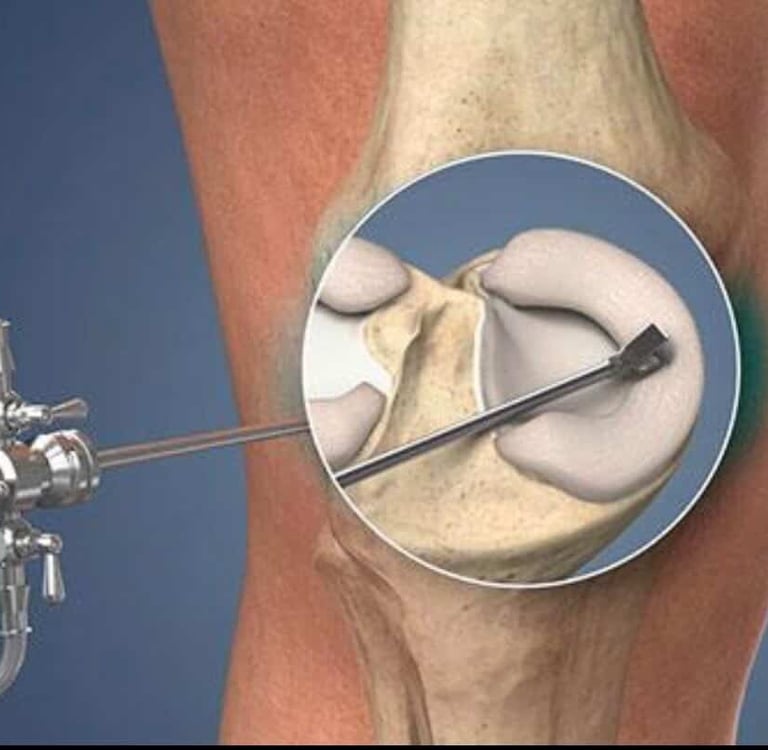

Advanced joint reconstruction using durable hip and knee replacement technology.

Reconstruction